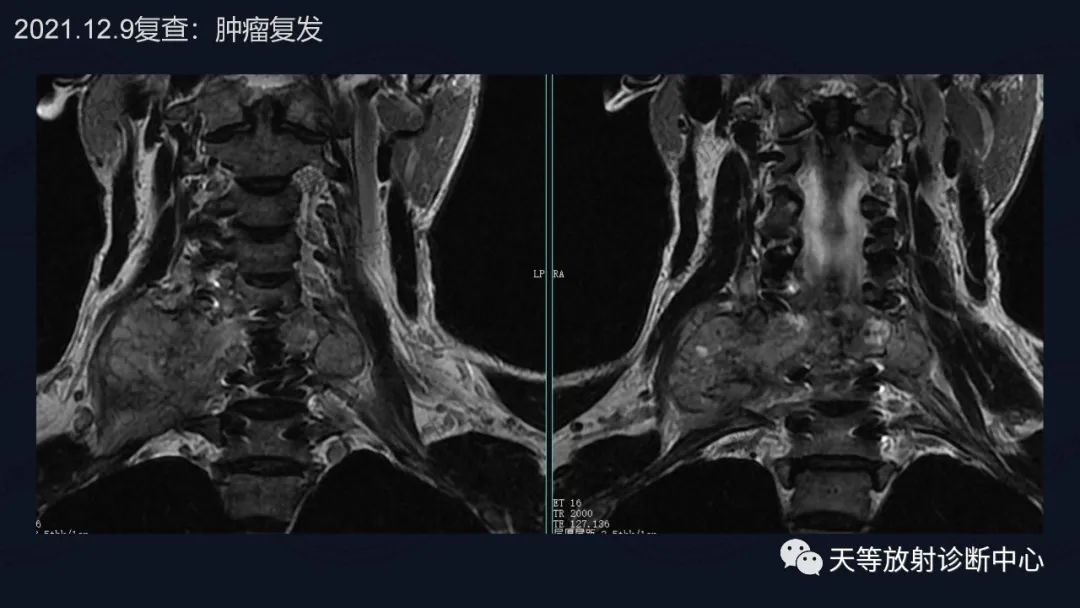

肿瘤复发,椎旁分叶状软组织肿块,内部信号不均,混杂信号,高低信号不等,内见线状小叶间隔。

DWI信号较高,内部钙化灶呈散在泥沙样低信号灶。

诊断软骨肉瘤复发。